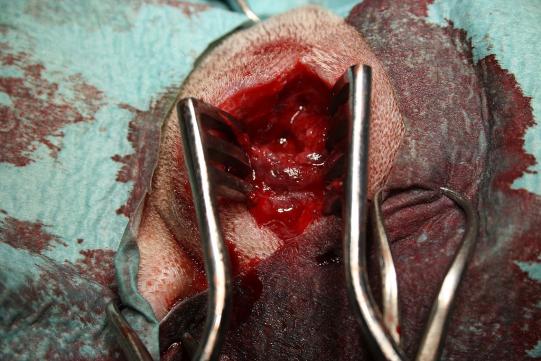

Nach einigen Tagen des Abwartens, in denen der Prozess reifen kann, wird Maya narkotisiert. Unter Ultraschallführung wird eine Kanüle zum beobachteten wahrscheinlichen Fremdkörper vorgeschoben. Entlang dieser Kanüle wird der Knoten dann chirurgisch eröffnet - in einer grösseren Menge Eiter findet sich dann tatsächlich eine Pflanzenrispe. Die Abszesshöhle wird ausgiebig gespült, die Haut wieder verschlossen und der Abszess mit einer Drainage versehen, damit der verbleibende Eiter abfliessen kann. Maya erhält ein Antibiotikum, Schmerzmittel sowie eine Halskrause, damit sie den Drain nicht auskratzen kann. Einige Tage später wird der Drain dann gezogen - die Schwellung ist schon praktisch komplett verschwunden und dem Hund geht es sehr gut. Einige weitere Tage später ziehen die Besitzer selber die verbleibenden Fäden; der chirurgische Schnitt ist gut verheilt.